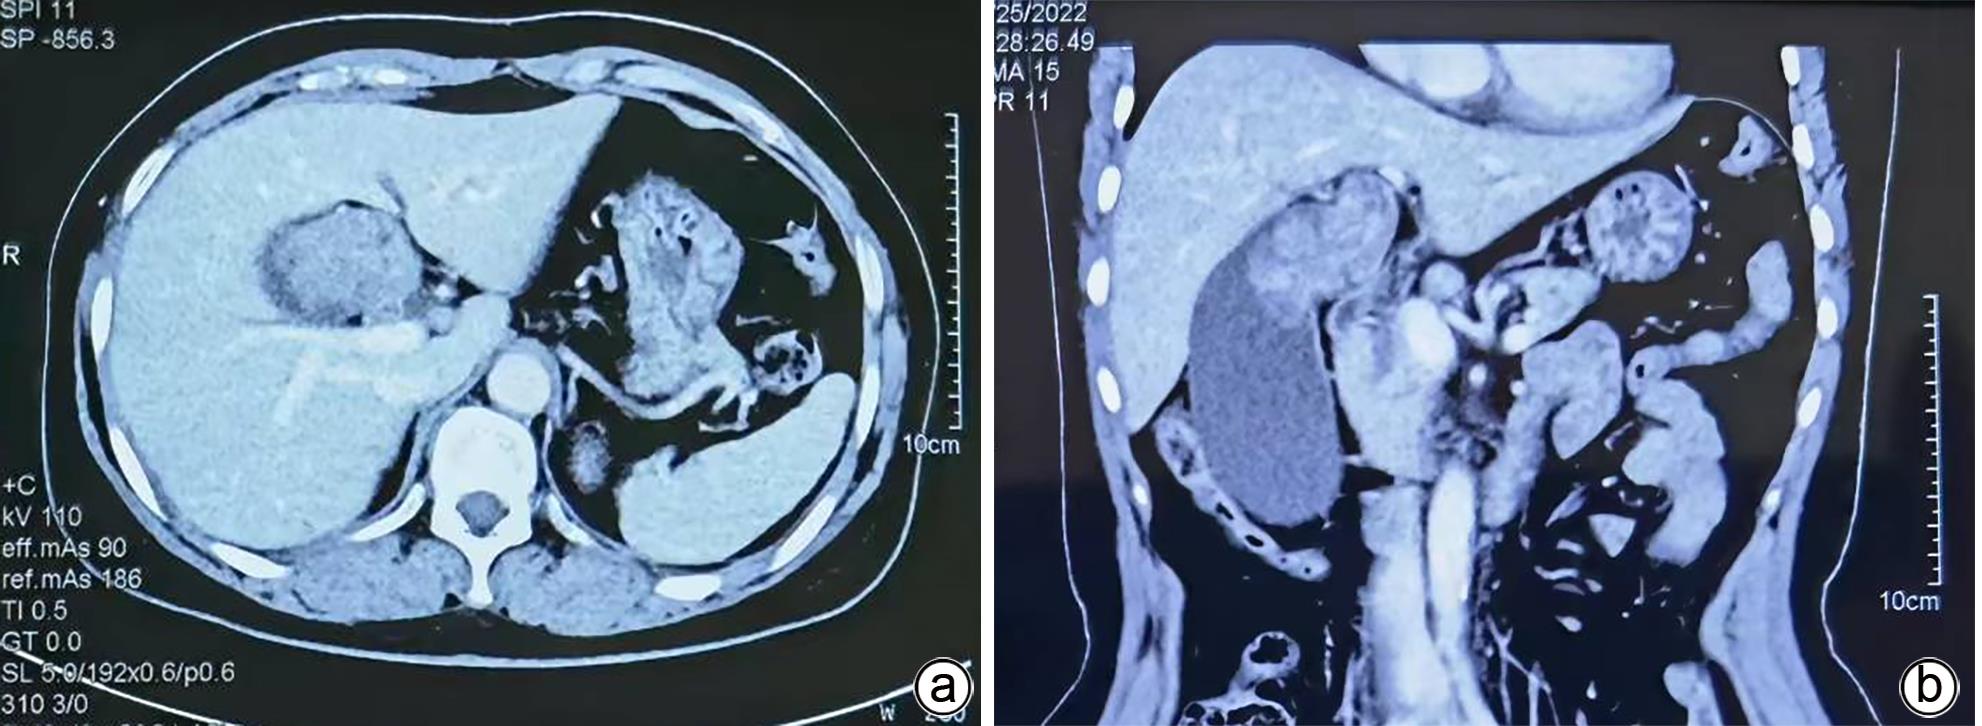

Giant adenoma of the gallbladder misdiagnosed as gallbladder carcinoma: A case report

Yuehua WANG, Hua JIANG, Lianghong TENG, Huanli DUAN, Bixiao CUI, Dongmei WANG

2024, 40(4): 794-796. DOI: 10.12449/JCH240424

Abstract(1183) HTML (564) PDF (1133KB)(65)

Abstract:

One patient with gallbladder mass had transient jaundice and was diagnosed with gallbladder carcinoma by abdominal ultrasonography, contrast-enhanced CT, MRCP, and PET-CT. Surgical exploration showed enlarged gallbladder and a mass in the neck of the gallbladder pressing against the hilum of the liver, with no manifestation of tumor invasion, and there were no signs of liver metastasis. Only cholecystectomy was performed for the patient. The pathological diagnosis was tubular adenoma of the gallbladder without carcinogenesis. This case is characterized by a large gallbladder tumor, without marginal infiltration on imaging or malignant transformation based on pathology.